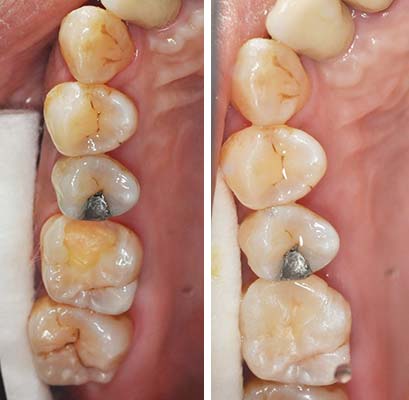

但是樹酯因為強度不足往往一段時間後,產生邊緣龜裂,與二次蛀牙這時候蛀牙範圍往往會比第一次更大,可以使用3D齒雕作修復, 提供牙齒良好的強度與美觀。

傳統金屬材料(銀粉)會熱脹冷縮,而且無法與琺瑯質連結在一起,太大的缺損在填補後經過一段時間容易與牙齒分開,導致二度蛀牙,導致齒質再破壞。

圖2較大的蛀洞可使用3D齒雕,保存較多牙齒結構,並提供足夠強度的支撐,恢復牙齒型態與功能。